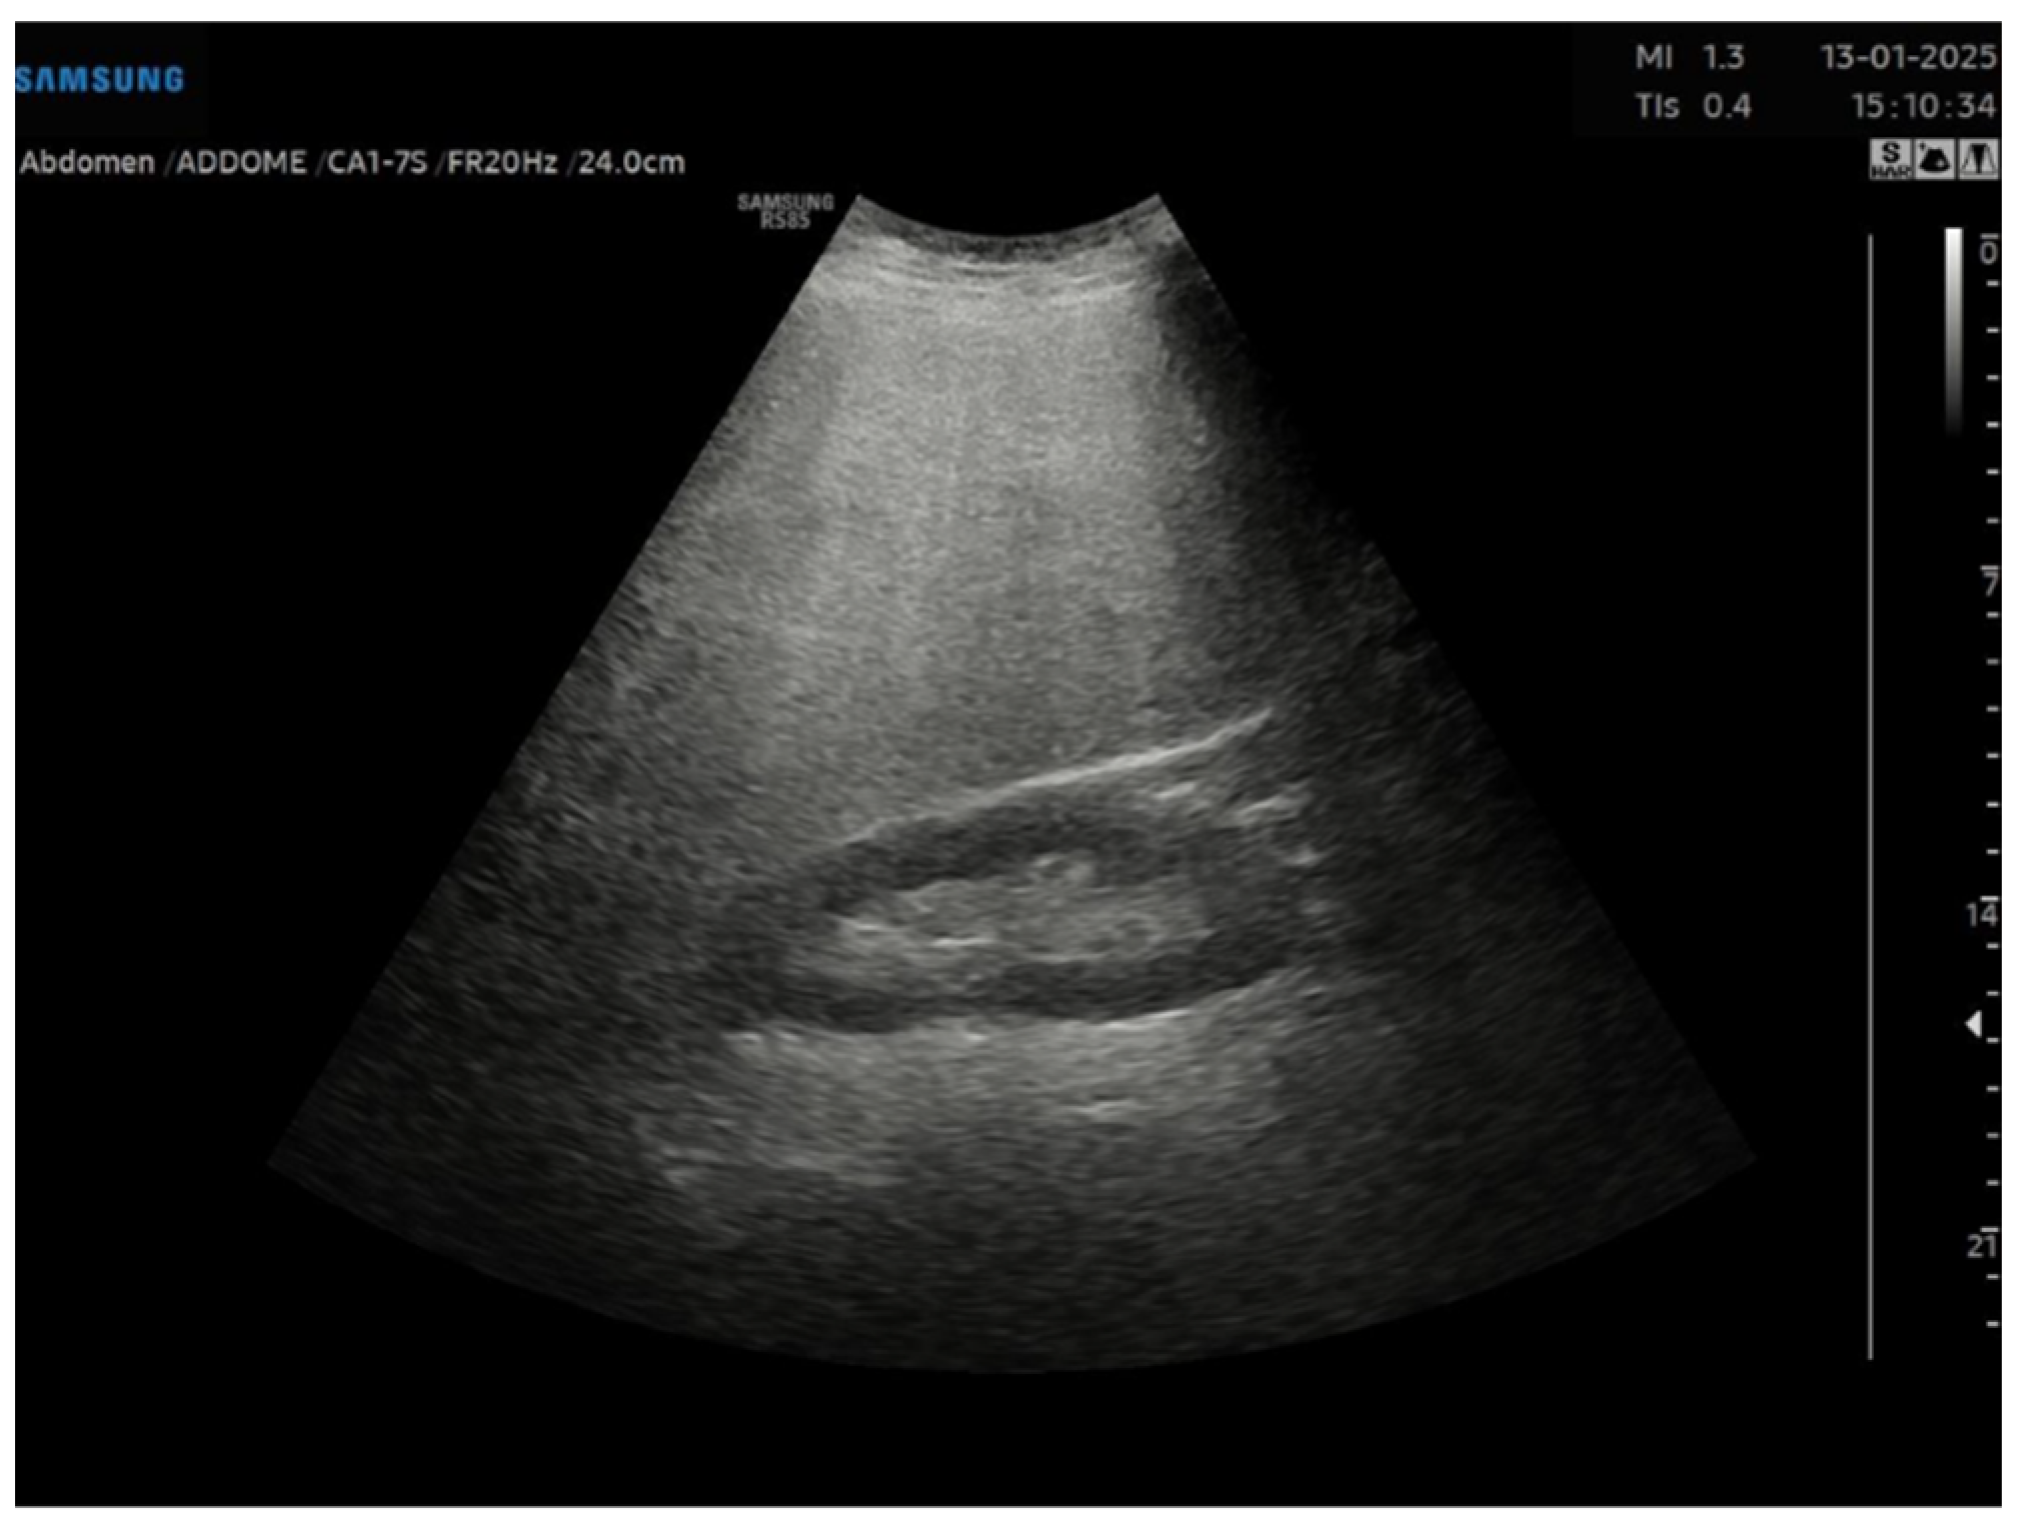

This is a cross-sectional observational study based on retrospectively collected ultrasound and clinical data. A total of 95 obese patients who underwent abdominal ultrasound examination as part of the preoperative assessment for potential bariatric surgery between November 2023 and April 2024 were evaluated. Ultrasound examinations were performed by expert echographers (with a minimum of 5 years’ experience in abdominal US) using Samsung RS85 Prestige system. The examination was performed after at least 6 h of fasting, with the patient in the supine position, using a right intercostal scanning approach. Each patient underwent conventional abdomen ultrasound with visual assessment of liver steatosis (Figure 1) and subsequently to the measurement of USFF with the Samsung CA1–7S (1 MHz–7 MHz) transducer. The ultrasonographic steatosis visual assessment and the USFF measurement were performed by different groups of operators in a blinded manner. TSI (Figure 2) and TAI (Figure 3) data were acquired and subsequently processed using proprietary algorithms developed and calibrated at the Samsung Medical Center [27,28]. These algorithms extracted relevant parameters, namely the attenuation coefficient and backscatter coefficient. A mathematical model grounded in established physical principles and incorporating empirical data, was then employed to translate these extracted parameters into an estimate of the liver USFF. Patients with clinical or morphological features of advanced liver diseases or cirrhosis, active viral hepatitis, alcohol use disorder, altered liver enzymes and heart failure were excluded. The collected data included age, gender, body mass index (BMI), TAI, TSI, USFF values, liver enzymes, comorbidities.

Figure 1. Visual assessment of severe liver steatosis in a 46 years old male patient with grade III obesity, type 2 diabetes, and hypertension.